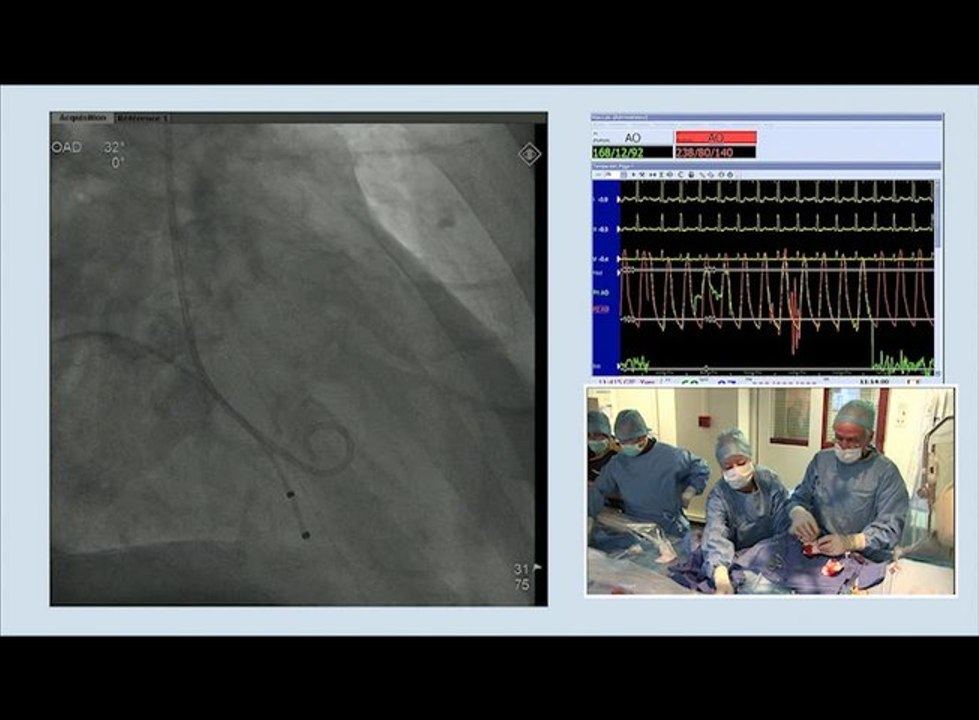

Hemodynamic & Angiographic Controls

Cardiology

/

Valvular

Aortic

Case in the box